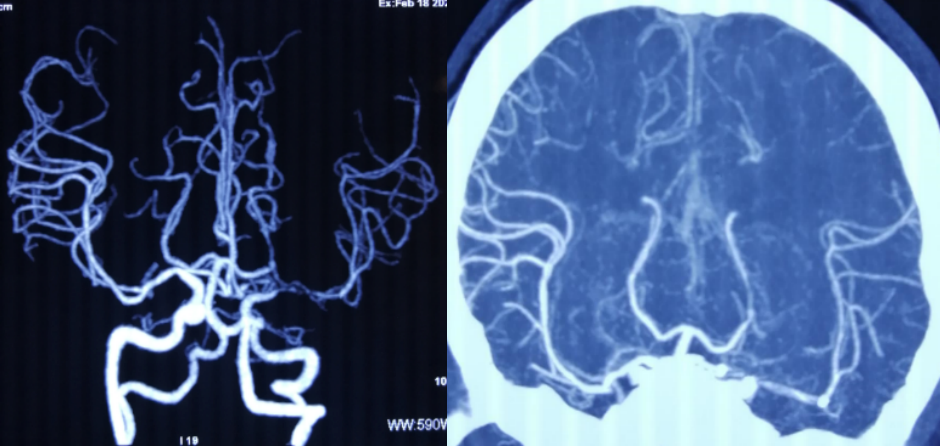

CTA示左侧大脑中动脉主干重度狭窄 2019.6天坛医院

CTP:MTT,TTP延长

2020.5 DSA左侧大脑中动脉重度狭窄

介入治疗后明显改善

术后4个月复查,CTA示支架近端可疑再狭窄 (2020.09,天坛医院)

术后9个月再次复查CTA示左侧大脑中动脉支架内重度狭窄 (2021.02.18天坛医院)